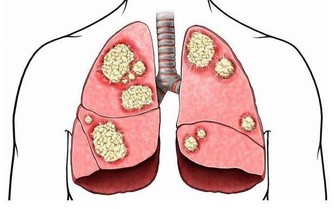

硫磺椒含有強致癌物,如果進入人體,會給腸胃、食道、粘膜等帶來刺激,

破壞消化系統和呼吸系統。長期食用,還會加大致癌風險。